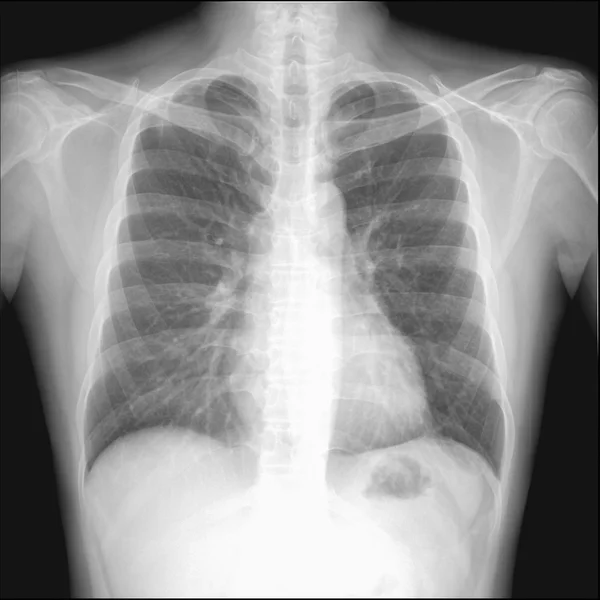

Пневмоторакс это состояние, когда плевральная полость легкого наполняется газом, который поступает туда через мельчайшие дефекты легких . Такая патология вызывает спадение пораженной . . .

Пневмоторакс на рентгенограмме: рентген-признаки плеврального воздуха Пневмоторакс на рентгенограмме проявляется просветлением с отсутствием легочного рисунка, вызванным скоплением . . .

Первичный спонтанный пневмоторакс встречается у лиц, не страдающих заболеваниями легких, как правило, у высоких худых подростков и мужчин возрасте 20-30 лет . Считают, что он вызван спонтанным разрушением . . .